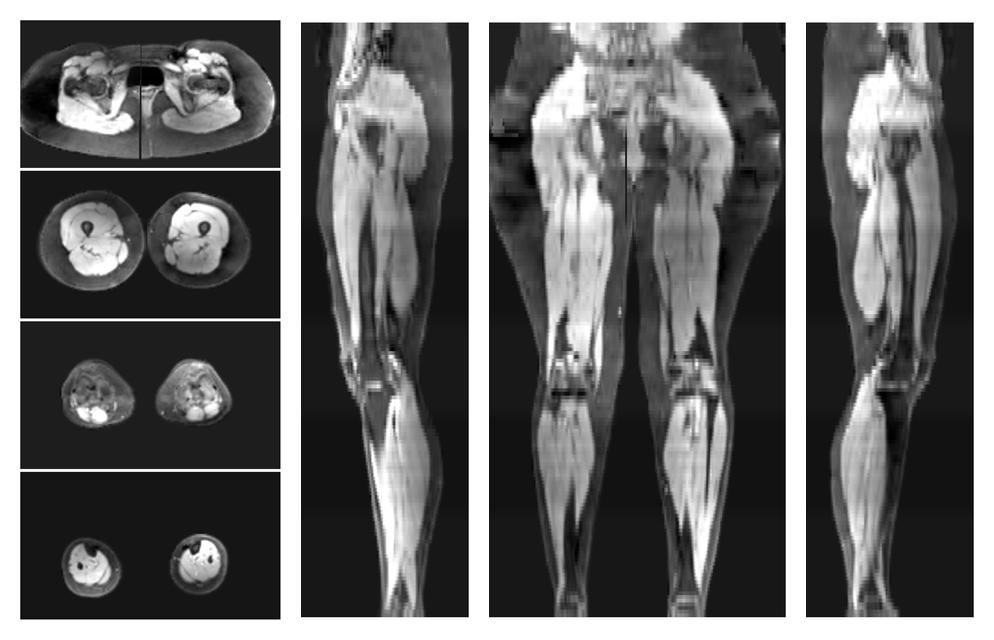

• Water only signal

The water part of the acquired multi-echo spin echo data.